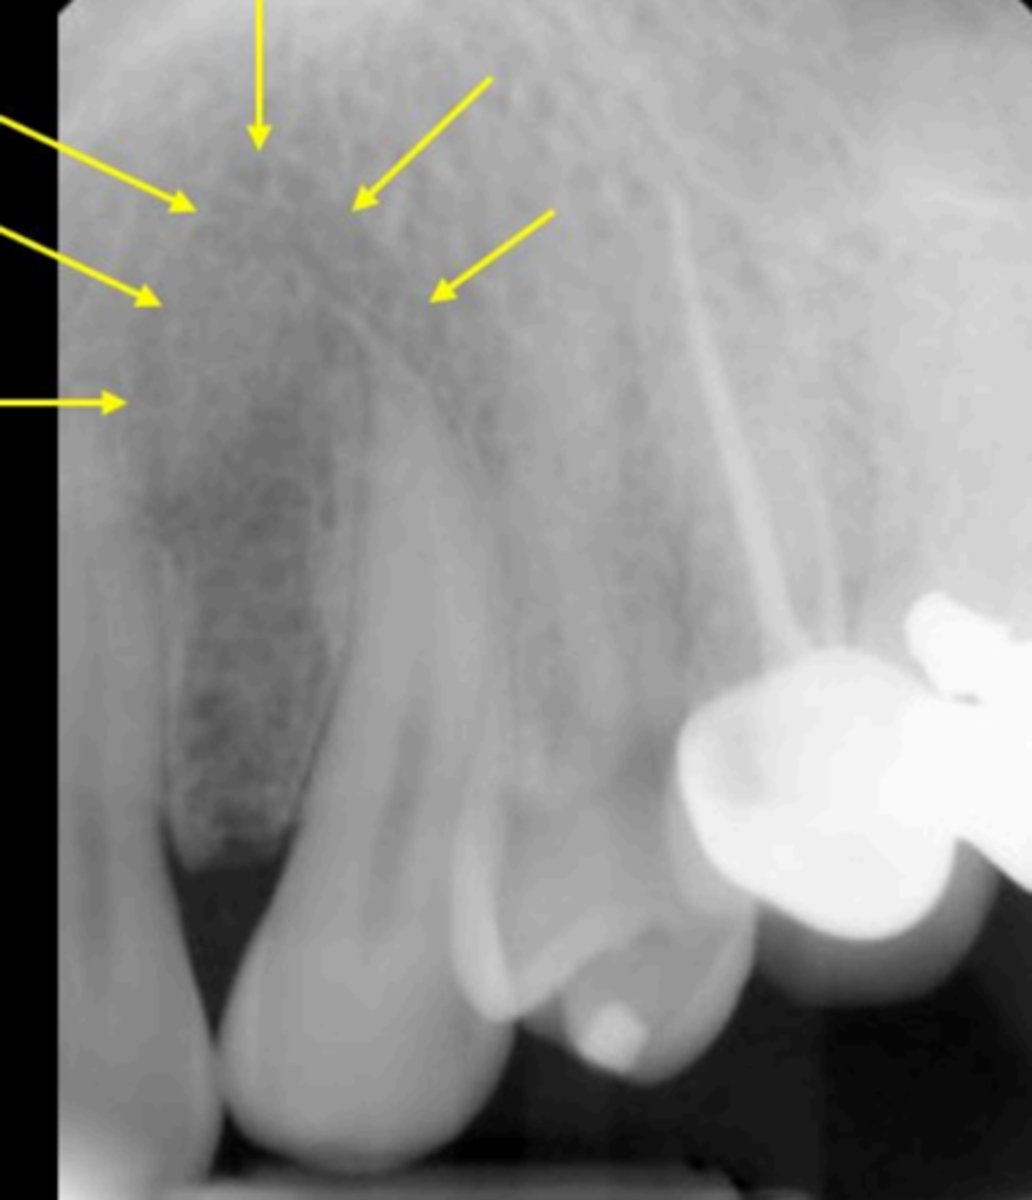

Zygomatic process of the maxilla

Name the curved, radiopaque structure indicated by the arrows.

<p>Name the curved, radiopaque structure indicated by the arrows.</p>

<p>Identify the structure</p>

6

New cards